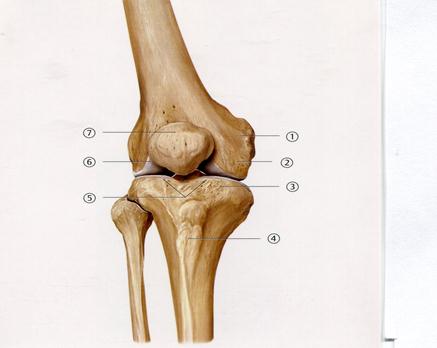

А. Латеральды толарсақ

+В. Медиальді толарсақ

С. Медильді, латеральды айдаршықтар

D. Кіші жіліншік басы

Е. Сүйекаралық жарғақ

38. Төменде көрсетілген суреттегі белгіленген № 7 анатомиялық құрылымды атаңыз.

А. Асықты жілік бұдырмағы

В. Буын беті

С. Медиальді айдаршықүсті

+D. Медиальді айдаршық

Е. Тізе үсті сүйегі

42. Төменде көрсетілген суреттегі белгіленген №5 анатомиялық құрылымды атаңыз.

А. Айдаршықаралық шұңқырша

В. Айдаршықаралық қырат

С. Латеральді айдаршық буын беті

D. Медиальді айдаршық буын беті

Е. Медиальді айдаршық